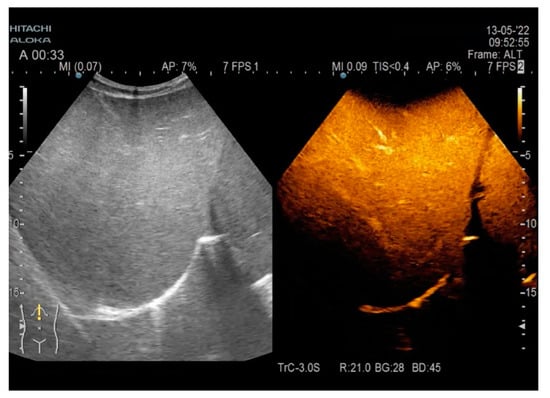

Chronic Calcifying Pancreatitis Associated with Secondary Diabetes Mellitus and Hepatosplenic Abscesses in a Young Male Patient: A Case Report

2. Case Report